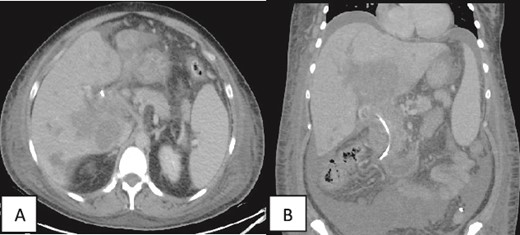

Contrast enhanced CT scan of the abdomen and pelvis was repeated post-PTC and showed multiple intrahepatic fluid collections suggestive of abscess formation and an increase in ascites (Fig. 4).

(A, B) Contrast enhanced CT scan of the abdomen and pelvis in axial and coronal sections in porto-venous phase status post-stenting showing that the hypo-vascular hypodense areas progressed compared to the initial CT with involvement of the liver parenchyma and hepatic hilum. Associated intrahepatic biliary ductal dilation and evidence of increased ascites was also noted. A pig-tail catheter tip is seen in the left lower quadrant.